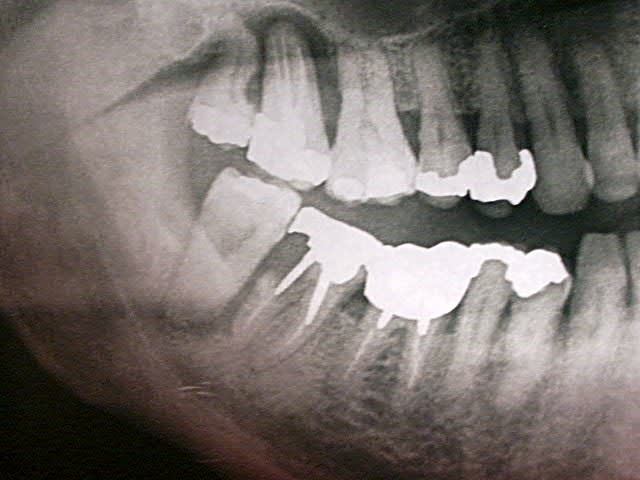

Manifestement alvéolyse horizontale généralisée, 25% de perte d'attache à 65 ans : je penche pour une parodontite chronique de l'adulte.

Suffisant s'il n'y avaient pas ces facteurs aggravants que sont les pulpectomies déficientes, couronnes débordantes et mal ajustées.

moi, c'est la 17 qui me chagrine le plus.

Cas typique (enfin je crois) où il est urgent de ne pas extraire, ni de se jeter sur le bistouri si on se met dans un "esprit paro" et que la compliance du patient est ok, sauf 18 (dent courte + carie M) et 17??? mais risque de déporter toutes les forces de mastication à G et c'est la 37 qui va devenir douloureuse.

ce cas présenté par tonio est un classique .....parodontite de l'adulte surement plus facteur occlusal ( cette patiente est en béance incisvo canine surement )

pour moi 17 18 28 perdues

48 pas très interessante si 18 pas conservée en plus elle est extrusée.....faire de l'odf alourdira je pense beaucoup pour un résultat pas forcemment supérieur tout en tenant compte de l'age

En dehors des secteurs postérieur, la paro semble maitrisable sans trop de probleme sur le long terme.

Donc, je me poserais vraiment la question de recontruire du fiable jusqu'au 6 ( donc, ext les 7 et les 8 ), avec un éventuel implant 36 si pas possible de stabiliser la lésion inter-radiculaire.

Pour moi : vu que la 17 est nase, j'éliminerai 18/17/ et comme la 47 n'est pas brillante, 47 et 48 aussi, sans remplacer aucune de ces dents : 1 molaire en haut et une en bas, c'est bon.

A gauche, c'est plus délicat : extraction des dents de sagesse, et reprise de tr canalaire de 26, 36 et 37 après, bien sûr, dépose des couronnes mal adaptées, et det et préparation initiale standard.

Mon plus gros doute concerne la 17: si je la vire, je vais entraîner une cascade d'extractions et répercuter toutes les forces de mastication à gauche. Mais bon... elle est douloureuse (impossibilité de mastiquer + mobilité) et l'alvéolyse semble totale. Je ne crois pas que l'on pourra la récupérer. Et en laissant un tel foyer infectieux, je risque d'entraîner la perte de la 16 aussi.

Ok pour virer 18 et 28. moins chaud pour virer 38 et 48 seulement si on garde la 17.

Je pense garder la racine M de 47 car encore bien accrochée et je ne sais pas s'il voudra faire des implants.

Bien que souhaitant pratiquer plus une paroméd, je me demande si une chir paro sur la 36 ne serait pas nécessaire. un avis?